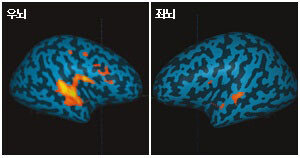

70대에도 ‘뇌 청춘’은 있다

나이가 들수록 뇌 기능은 저하한다. 기억력은 30대부터 떨어지기 시작한다. 공간탐지력도 기억력과 관련된 뇌 부위인 해마의 영향을 받는데, 이 역시 약해진다. 눈앞의 일에 집중하는 실행기능 능력 또한 줄어든다. 청력 등 감각정보 능력…